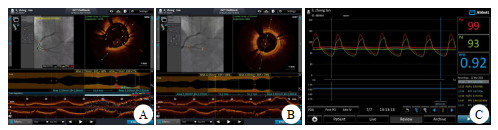

病例2,女,61岁。持续性心前区疼痛52 h,加重15 h,心电图提示:前壁、下壁ST-T改变(图 5)。cTnI 19.25 ng/mL,CK-MB 98.2 ng/mL(图 6),以非ST段抬高型心肌梗塞收住。评估后急诊PCI示罪犯血管OM 100%(图 7A),打通后置入2.25 mm×31.00 mm支架,PDA起始部95%狭窄(图 7B),FFR 0.78,LAD中段狭窄70%(图 7C),FFR 0.84(阴性),于PDA放置2.75 mm×29.00 mm支架,OCT测定支架远端膨胀不全,近端贴壁不良(图 8A),分别后扩球囊反复扩张,OCT再次检查无膨胀不全及贴壁不良现象(图 8B),FFR 0.92(图 8C),心肌酶趋势如图 6所示。

| A为PDA支架远端膨胀不全,近端贴壁不良;B为反复球囊后扩后膨胀不全及贴壁不良消失;C为后扩支架后PDA-FFR 0.92 图 8 病例2的PCI前后FFR及OCT检查结果 |